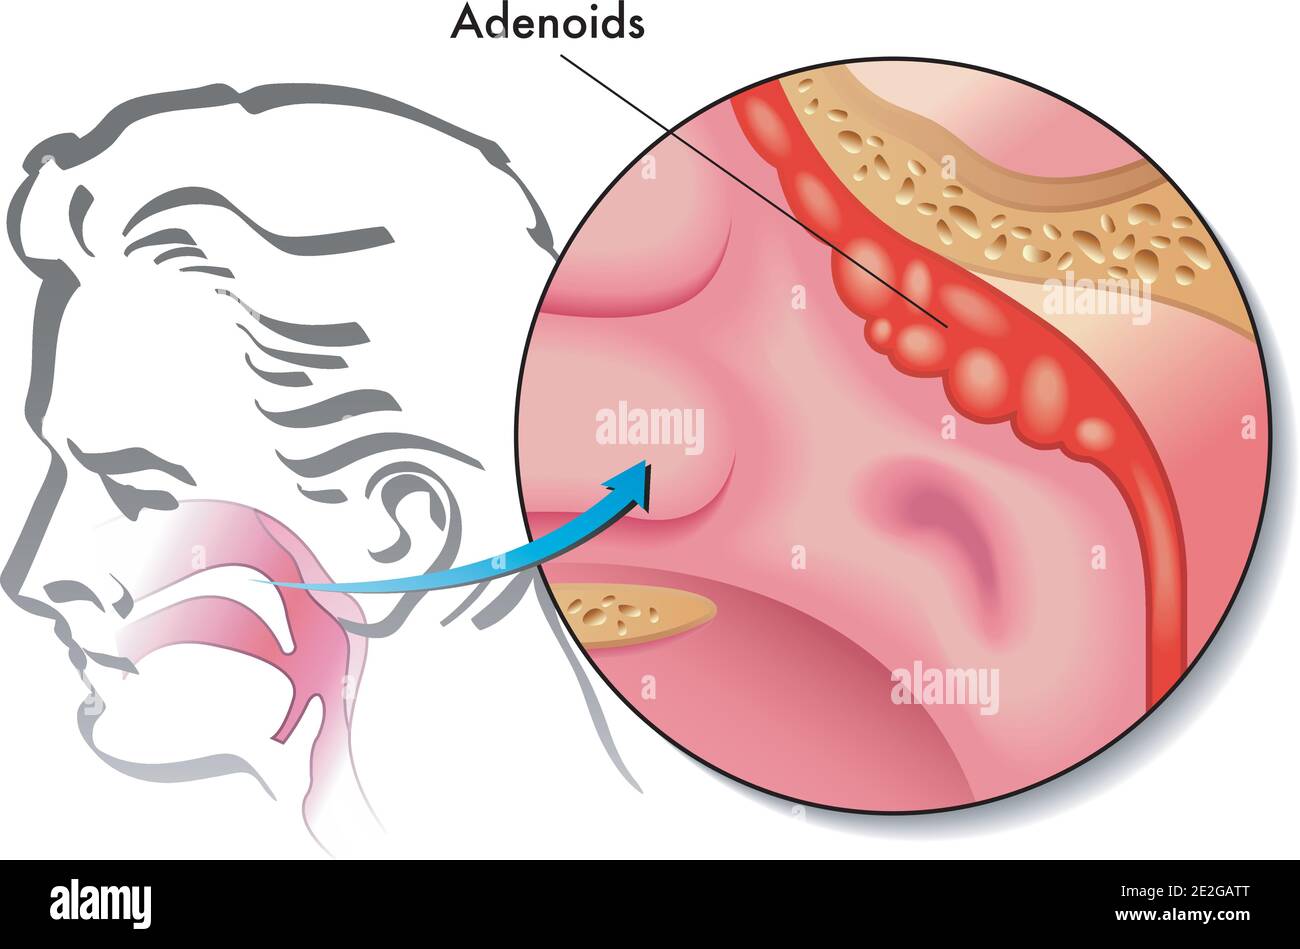

Medizinische Illustration der Adenoide Stock Vektorhttps://www.alamy.de/image-license-details/?v=1https://www.alamy.de/medizinische-illustration-der-adenoide-image397427544.html

Medizinische Illustration der Adenoide Stock Vektorhttps://www.alamy.de/image-license-details/?v=1https://www.alamy.de/medizinische-illustration-der-adenoide-image397427544.htmlRF2E2GATT–Medizinische Illustration der Adenoide